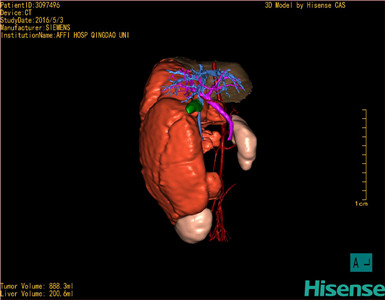

将0.625mm双源薄层CT资料的静脉期和动脉期Dicom格式文件导入海信CAS系统。

通过调节窗宽窗位调整CT序号,对肿瘤,肝实质,胆囊,下腔静脉,肿瘤,肝动脉、门静脉及肝静脉等进行三维重建;系统自动计算肿瘤体积和肝脏体积。(模拟手术操作,自动计算切除肿瘤体积。

术前三维重建:

重建图片